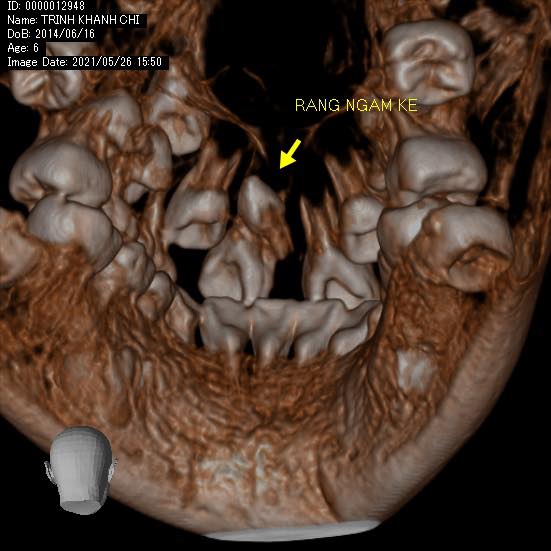

BN đến với than phiền từ bố mẹ rằng hai răng cửa vĩnh viễn của con mọc lên mỗi bạn xoè ra một hướng khác nhau ko ai chịu gặp ai.

Nếu nguyên nhân chỉ là phanh môi bám thấp thì phương án giải quyết lại nhẹ nhàng hơn hẳn. Nhưng ẩn sâu sau màn mưa mà mắt thường không thể nhìn thấy là một bạn răng thừa ngầm mọc lộn ngược giữa kẽ hai răng 11 và 21 làm tách đôi chúng ra. Và nếu không chẩn đoán đúng thì dù có đưa phanh môi về vị trí bám đúng thì chúng mãi mãi cũng vẫn chưa thể gặp nhau được.

Điều đáng nói ở đây là sự quan tâm của bố mẹ đã phát hiện sớm vấn đề của con trước khi nó quá trầm trọng. Sự dũng cảm, hợp tác và hiểu chuyện của một cô bé 7 tuổi làm bác sĩ quá sức bất ngờ.

Thương con gái, lo lắng con bị đau sau quá trình hậu phẫu. Nhưng cuối cùng thì hai bác cháu ta đã chiến thắng bạn răng xấu xí để lớn còn đi thi hoa hậu con gái nhỉ 👍🏻👍🏻👍🏻👍🏻💙👧🏻